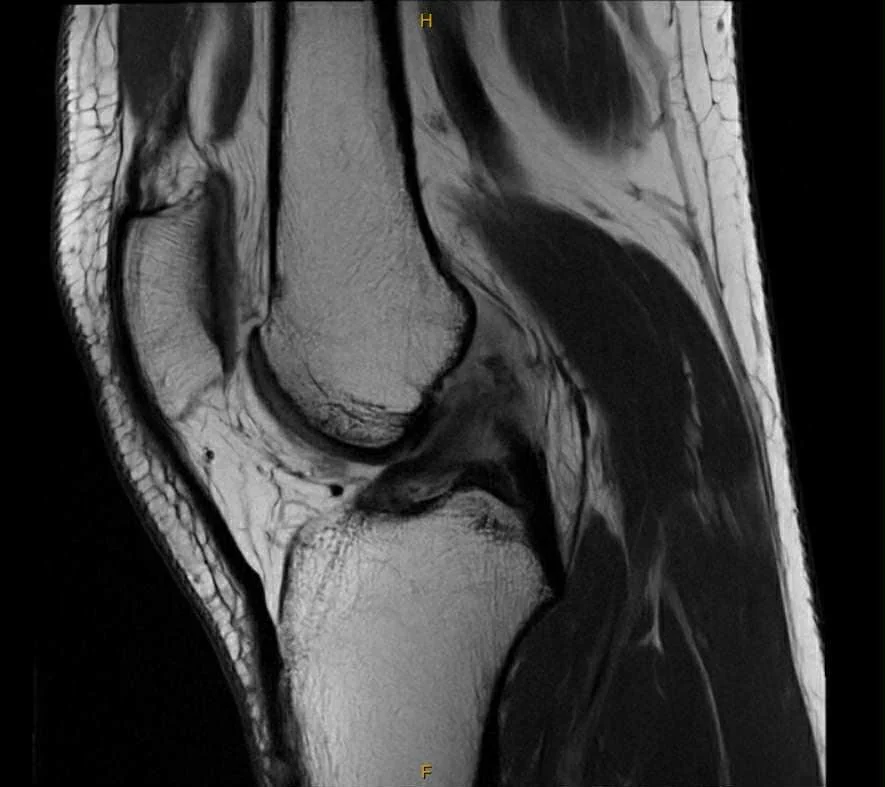

For me, that moment of truth is the week 12 MRI — the final boss of the CBP. Until then, I simply don’t know how everything has gone.

After twelve weeks of a knee locked at 90°, watching my quads slowly disappear, surviving boredom in the gym, getting opinions thrown at me like and generally living inside the protocol... The MRI is here. The moment where we find out is the ACL starting to heal?